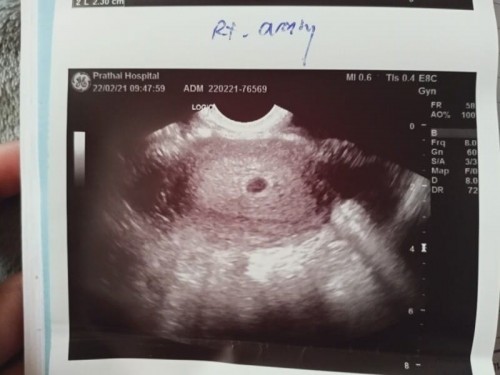

ท้องแรกค่ะแม่ๆ แต่ว่าทดสอบการตั้งครรภ์เจอวันที่18 ก.พ หนูได้ไปฝากครรภ์ที่ รพ.วันที่22 ก.พ และหมอก็อัลตร้าซาวด์ดูค่ะแต่ว่าไม่พบถุงตั้งครรภ์ เลยส่องทางช่องคลอดก็ยังไม่พบ หมอเลยบอกว่าอีก 1 สัปดาห์ค่อยมาอัลตร้าซาวด์ซ้ำค่ะ หนูไม่สบายใจค่ะ หนูกังวลใจมากเลย หนูกลัวค่ะแม่ๆ แต่ไม่มีอาการเจ็บท้องหรือมีเลือดออกเลยนะคะ #ขอคำแนะนำหน่อยค่ะ #ท้องแรกคะ #ขอบคุณล่วงหน้านะคะ